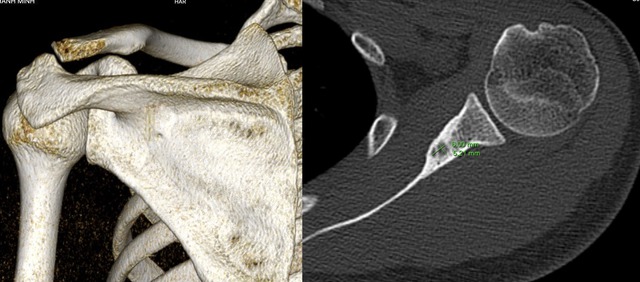

Trực tiếp điều trị ca bệnh, TS.BS Nguyễn Ngọc Cương (Trưởng khoa Can thiệp điện quang – Bệnh viện Đại học Y Hà Nội) cho biết: Khi đã phát hiện ra vị trí tổn thương, các bác sĩ về ngoại khoa khá “e ngại” về ca phẫu thuật này. Bởi tổn vùng xương là một ổ rất nhỏ chỉ có 5mm nằm ở trong xương vai. Trong khi đó xương vai là một xương dẹt rất khó xác định được vùng tổn thương, đây gần như là một phương án không khả thi.

Ê-kíp bác sĩ sử dụng kim chuyên dụng và sóng cao tần để can thiệp khối u.

Tại Bệnh viện Đại học Y Hà Nội, bệnh nhân đã được thực hiện đốt sóng cao tần dưới hướng dẫn của hệ thống DSA. Chia sẻ về ca phẫu thuật, TS.BS Nguyễn Ngọc Cương cho biết: "Ê-kíp sử dụng kim chuyên dụng để định vị chính xác tổn thương, sau đó dùng nhiệt của sóng cao tần để triệt tiêu hoàn toàn khối u trong xương.